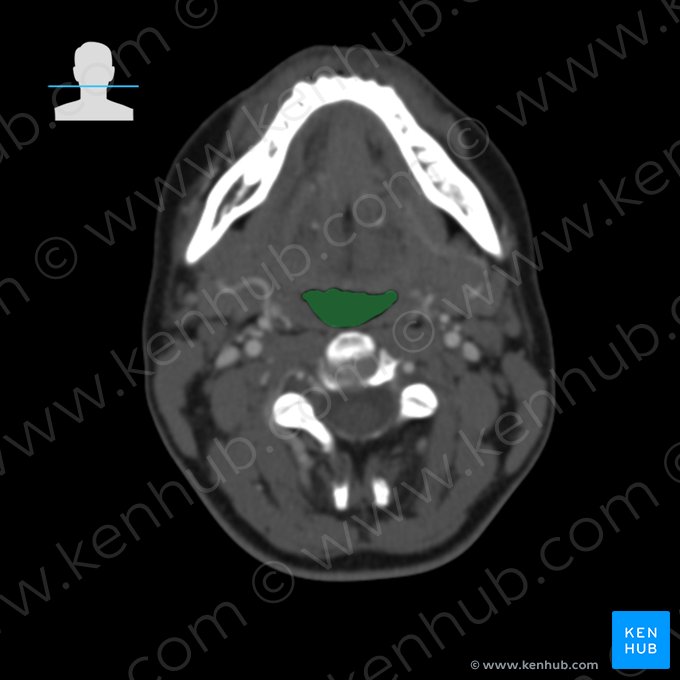

Le scanner ou tomodensitométrie axiale du cou nous permet de mieux comprendre les relations anatomiques de ces structures importantes et sont utiles à l'identification de multiples processus pathologiques qui peuvent survenir dans cette région.

Les images ci-dessous vous montrent les principales structures du cou vues sur l’imagerie.